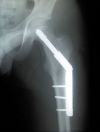

13.4 jsem si na Točné sjel takovej jeden hezkej sjezdík, vesele si skočil a užil si to, a jak tak pak pokračuju po zelené a chci odbočit na pěšinu k letišti, co se nestalo.. normálně jsem upad. Nechápu to, na širokánské cestě, kde jsem odbočoval snad tisíckrát. Trvalo to předlouho, než se svět zastavil, přikrčeně jsem ležel pár vteřin a zjistil  jsem, že se nemůžu hnout, převalit, nic. Po dlouhé době jsem přes velkou a nekompromisní bolest v kyčli zaujal jakous polohu. A zjistil, že bez záchranky to nepůjde, ani náhodou. A zavolal. Pak přijel pan Novák, cyklista,  a dělal mi skromnou ale milou a pomocnou společnost do příjezdu záchranky, trvalo to přes hodinu, užil jsem si šok, no nic. Do příjezdu záchranky? No, on je les na Točné uzavřen závorami a přes ně se záchranka ani policie nedostanou. A tak pánové od záchranky drkotali s nosítky s malinkými kolečky, vhodnými tak na dlaždice pražských domů a asfalt chodníků,  asi kilometr a půl po kamenité cestě. A nadávali. Nicméně mě pak naložili, nafoukli dlahu a vytlačili zpět ten kilometr a půl. Drkotalo to. Velká záchranka nemohla naložit kolo, je to proti předpisům, a tak jsme čekali další půlhodinu na policii, ti mi kolo odvezli do nemocnice. Díky jim a panu Novákovi a záchranářům, docela mi to pomohlo :o). Zkrátím o: nemocnice, operace, berle, rehabilitace. Zlomenina kosti stehenní blízko krčku. Po týdnu mě vyexpedovali z chirurgie v Krči. Žiju sám a můžu konstatovat, že je to tedy pohoda, třeskutá,  v rámci možností. Jen se umýt dojít na WC to bylo jako vylézt na nějakou horu, zpočátku, teď už to zvládám lépe. Chirurgové v Krči to řešili nějak podobně jako tady: http://www.med.wayne.edu/…/DHS-DRH.JPG – pokud mohu jako laik posoudit. Když jsem to uviděl, nevěřil jsem, že mi tam našroubovali tolik železa (a to v Krči nepoužili o ten samostaný šroub méně). 6 týdnů bude noha bez zátěže, a pak se pozvolna začne se zatěžováním, prý. Sem píšu, protože bych uvítal doporučení jak rehabilitovat, určitě to tu někdo prožil také. Trochu  přec jen s mírou, o nekrózu kyčelního kloubu  nestojím. Zatím se procházím s podpažními berlemi, co na to říkaj ruce se ani neptejte, cvičím lehce, ohýbám nohu, a učím se pokoře a trpělivosti.   Děkuji za vaše doporučení, zkušenosti, rady.

Přidávám se po v podstatě stejném zákroku, operace minulou středu, od soboty doma.

Popis a pár cviků zde např.

https://www.physio-pedia.com/…_Screw_-_DHS